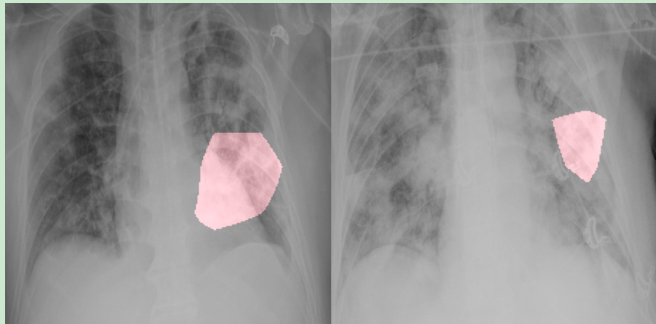

7、Lung Infection Quantification of COVID-19 in CT Images with Deep Learning

这篇来自上海交通大学,由沈定刚指导。主要是做3D CT分割,对感染区域进行分割。

数据集: 249名COVID-19患者进行训练,300名COVID-19患者进行验证。

方法: 提出了 VB-Net,主要是改进了V-Net。